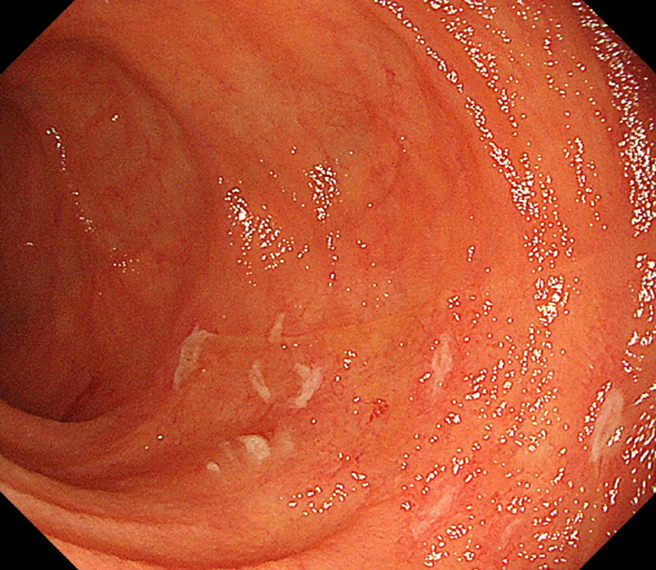

大腸内視鏡検査における縦走潰瘍および敷石像

大腸型クローン病患者の結腸において、数条の縦走潰瘍と、その周りに敷石像を認める。